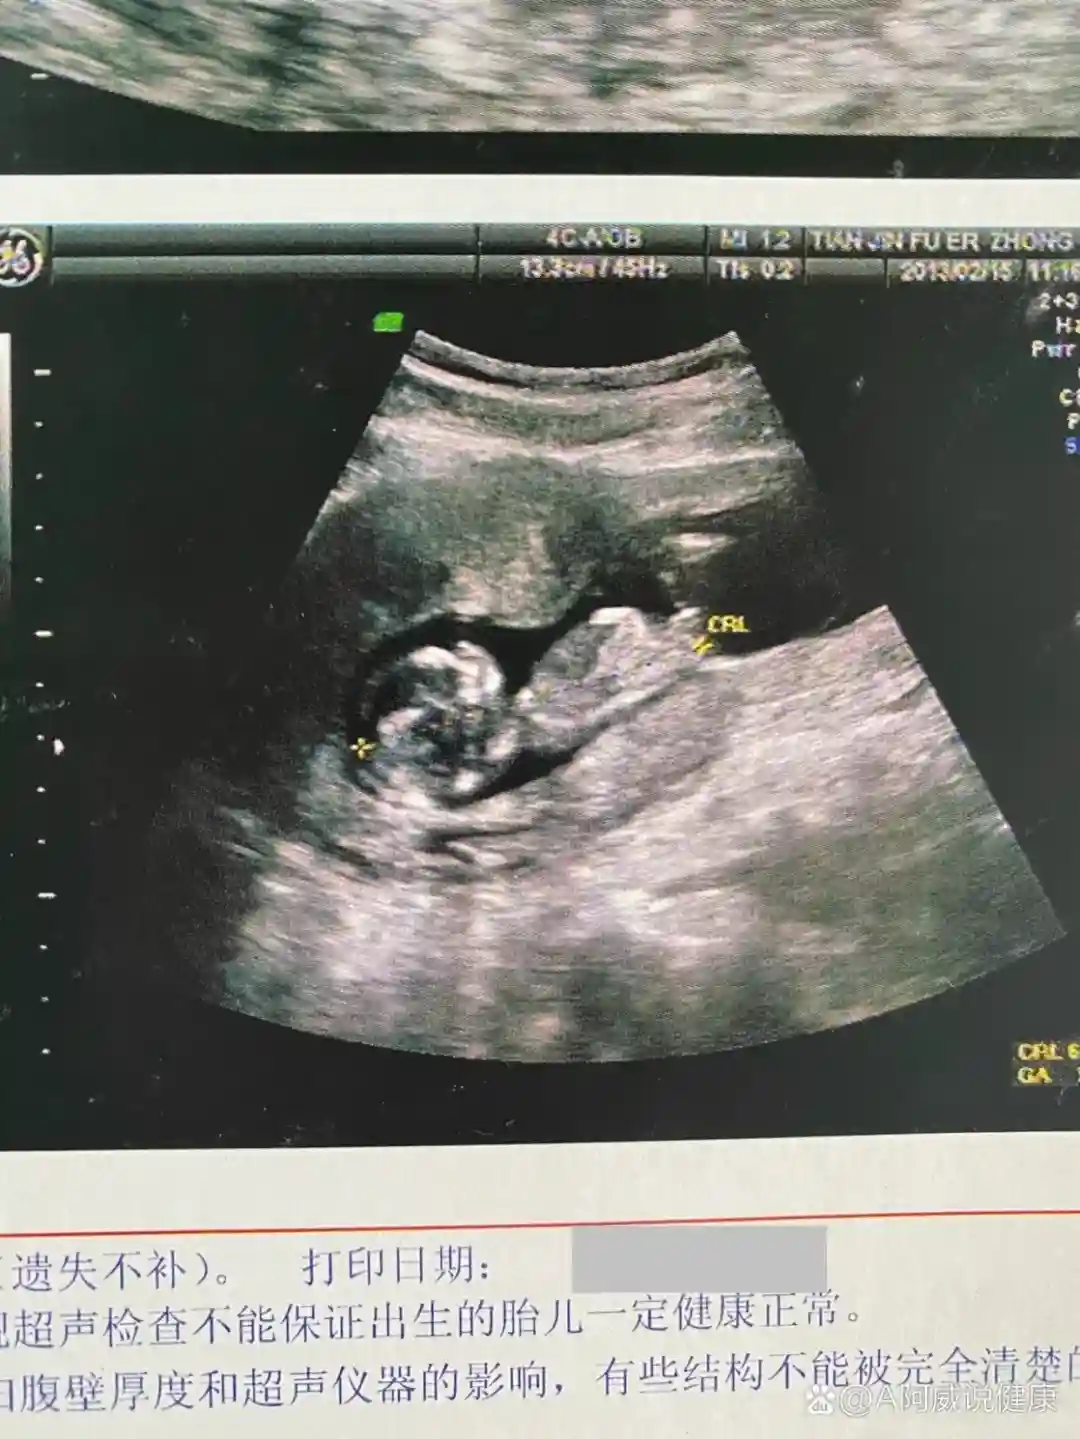

NT图看nub点,翘为蓝,平为粉 ( 准✅ )

12w的b超图就能看到小人儿了,根据🍠上其他姐妹分享nub点

的观点看法,我们好像是翘的。(nub点我不太拿得准)